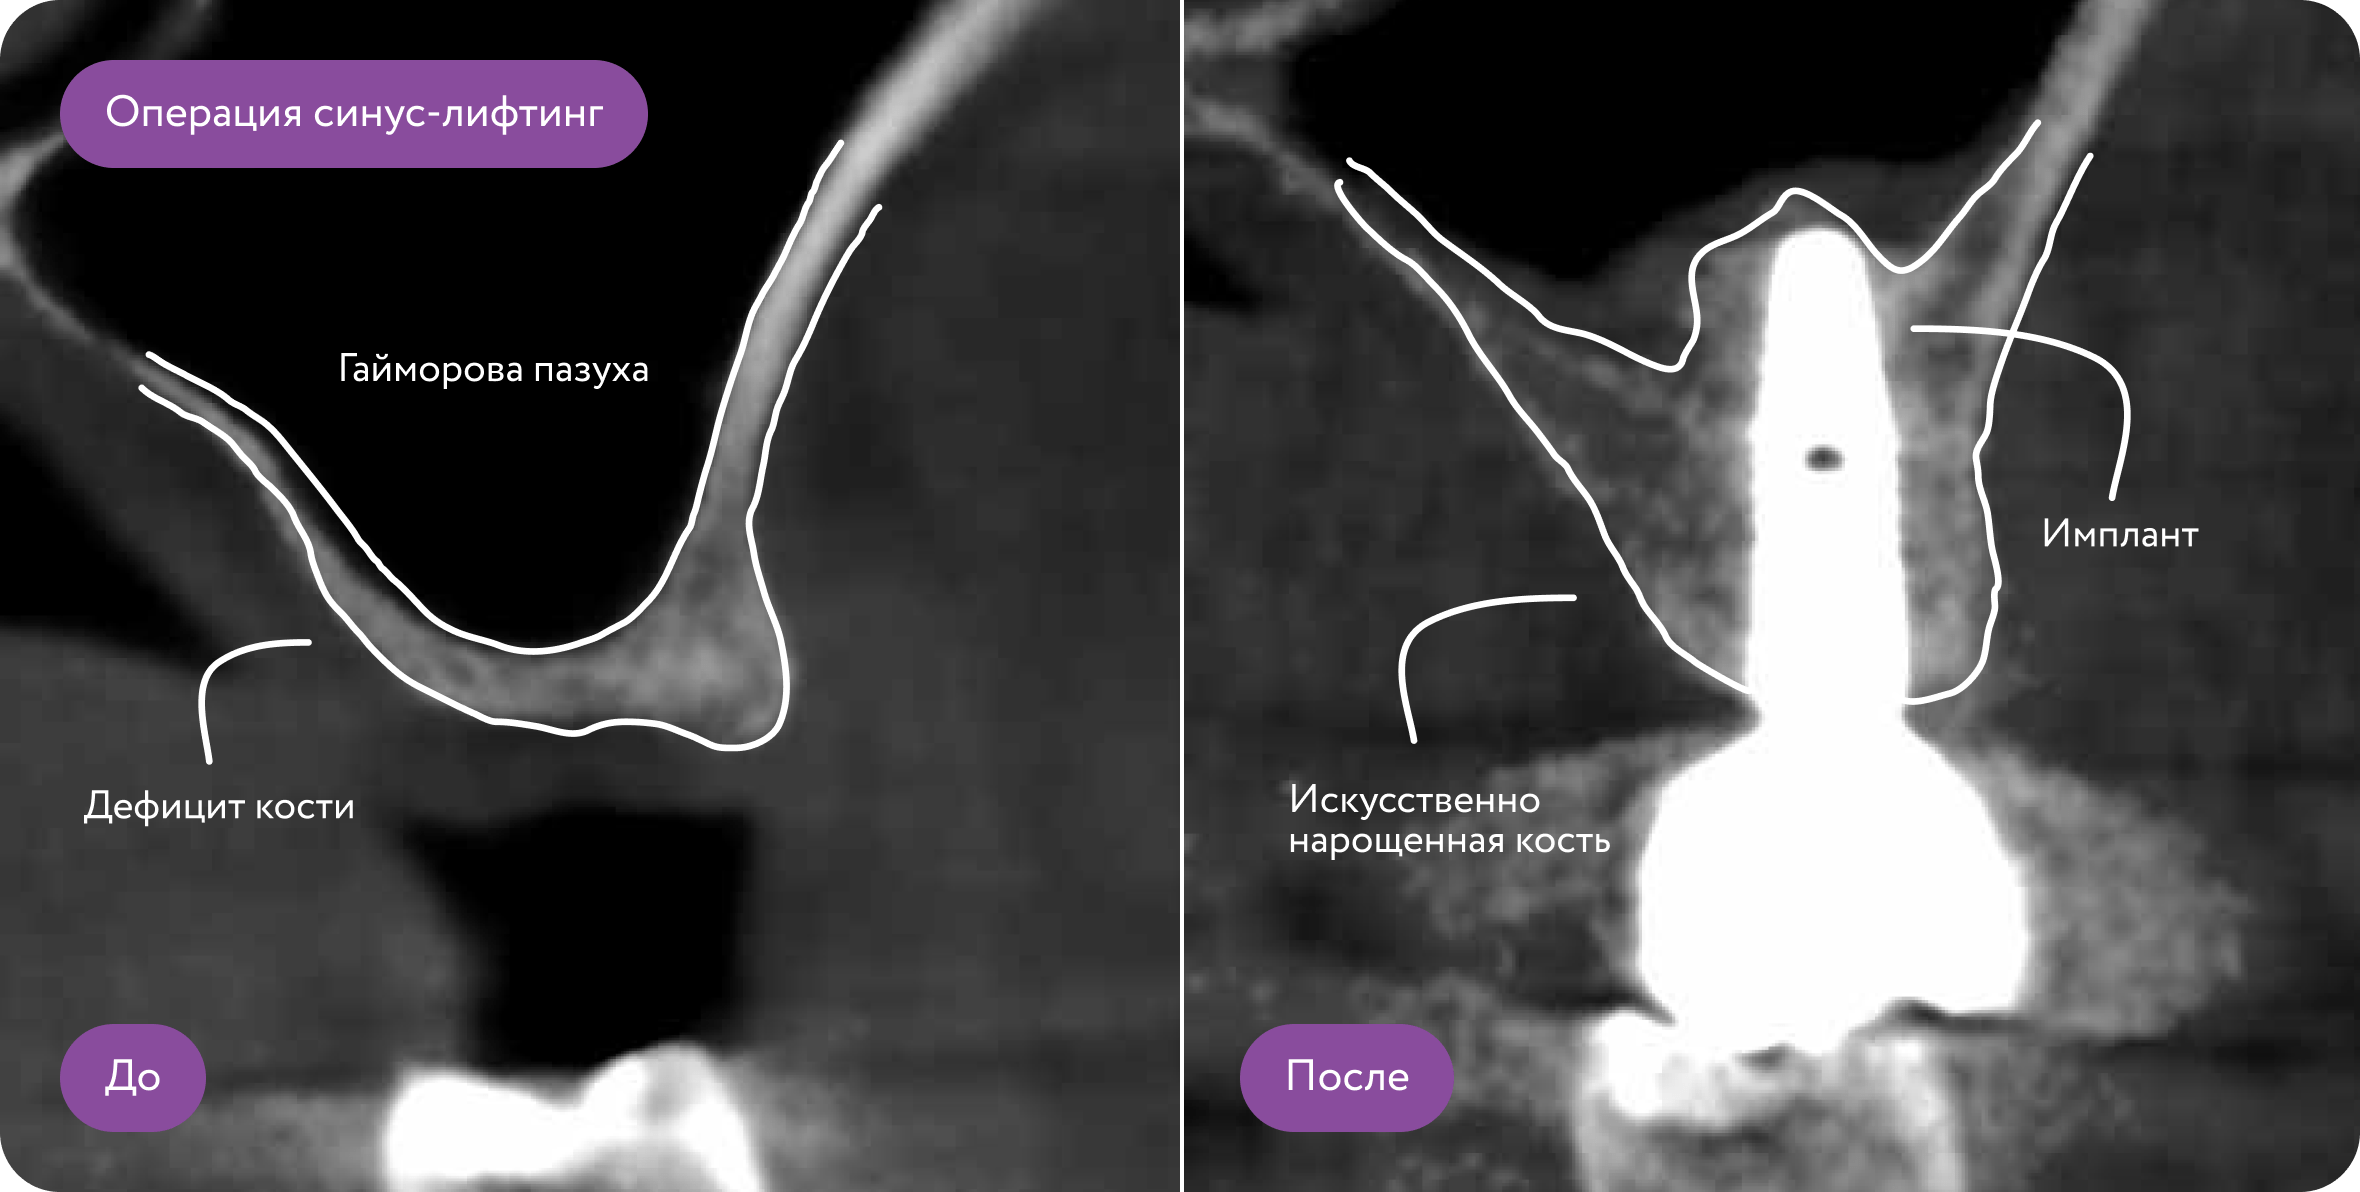

Для чего делают костную пластику?

Часто бывает, что после удаления зуба кость атрофируется, и нет условий для установки импланта. Требуется костная пластика - наращивание костной ткани с использованием искусственного костного материала